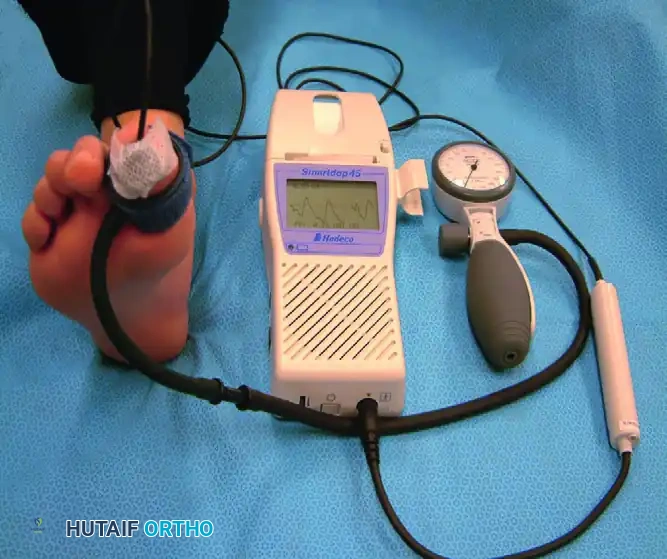

Clinical signs of vascular insufficiency include absent pedal pulses, trophic skin changes (hair loss, shiny skin), and a history of claudication. Non-invasive vascular testing is mandatory. Because medial arterial calcification (Mönckeberg's sclerosis) can falsely elevate the Ankle-Brachial Index (ABI), Toe-Brachial Index (TBI) and toe systolic pressures using photoplethysmography (PPG) are more reliable indicators of pedal perfusion.

Measurement of toe systolic pressure with a manual PPG unit. A toe pressure >40 mm Hg is generally required for predictable wound healing.